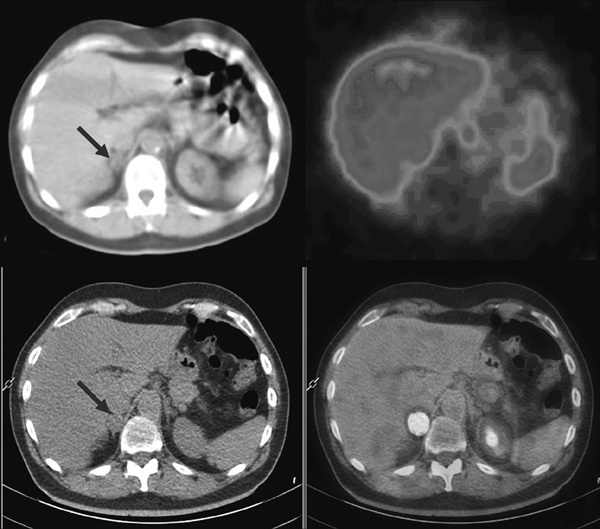

A wide range of PET tracers, both specific and non-specific for chromaffin tumors, have been applied for imaging Pheo/PGL.35,53,54 Generally considered, PET agents provide excellent tumor imaging and show a tumor-to-background ratio greater than 123I-MIBG; moreover, with PET technology a higher spatial resolution is obtained. Accordingly, with PET more lesions are detected with higher contrast. Other advantages versus MIBG scintigraphy are: less radiation exposure, no need of thyroid blockade or of withdrawing medication for many of them and immediate imaging after injection. However, except for 18F-FDG, PET agents do not yet have widespread clinical use due to their high cost and limited availability. Specific agents (124I-MIBG, 11C-hydroxyephedrine, 18F-DOPA, 18F-dopamine) show diagnostic specificity similar to MIBG. Among these, 124I-MIBG is used mainly for dosimetric estimates before 131I-MIBG therapy.55 Non-specific PET agents that can be used for imaging Pheo/PGL include 68Ga-somatostatin analogs (somatostatin receptor status) and 18F-FDG (glucose metabolism).54,56 Table 2 depicts diagnostic profiles from studies comparing PET tracers and MIBG in Pheos/PGL on a per-patient and on per-lesion basis.43-47,52,57-76 According to recently published EANM guidelines for radionuclide imaging of Pheo/PGL, MIBG is as sensitive as PET agents (mainly the specific ones) in patients with non-metastatic sporadic Pheo even in rare non-hypersecreting tumors.22 Therefore, in this group of patients PET agents should be used only for MIBG negative cases and/or in the presence of interfering medications (Figure 2).22 A real advantage of PET agents over MIBG seems to be with regard to malignant disease, partly due to the ability of PET-CT scanners to detect and localize very small lesions throughout the body. Literature data support the superiority of various PET tracers (in particular, 18F-Dopamine, 18F-DOPA and 18F-FDG) over 123I-MIBG to assess disease extension in patients with malignant Pheo/PGL, even though with different behavior in the different clinical syndromes on the basis of specific gene mutations.45,47,67,70,77 In any case, in these patients MIBG imaging provides unique information, allowing the selection of patients suitable for 131I-MIBG therapy. For head and neck paragangliomas, where MIBG scintigraphy usually fails, 18F-DOPA yields excellent results being most sensitive for small tumors.45 Preliminary data seem to indicate a primary role of 68Ga-labeled somatostatin analogs not only in patients with head and neck PGL (as expected) but also in those at high risk of PGL and metastatic disease.75,76

Figure 2. Top: 123I-MIBG SPECT-CT in a patient with Pheo in the right adrenal gland. The right adrenal mass is evident at low-dose CT (left image, red arrow) and shows no significant uptake at MIBG SPECT (right image). Bottom: 18F-DOPA PET-CT showing increased tracer uptake in the right adrenal mass (right image).